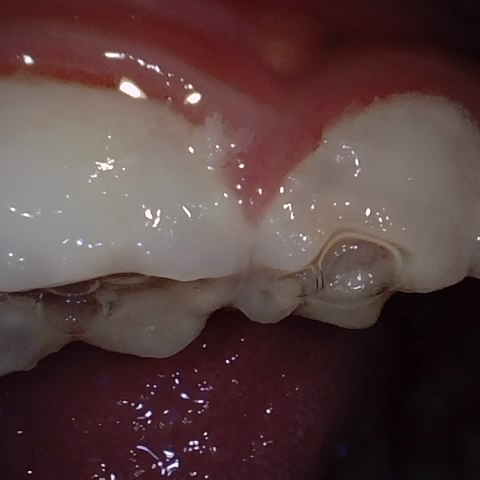

Image 264 / 400

NHD25463

Annotated as "Good"

Original Image Rendering Image